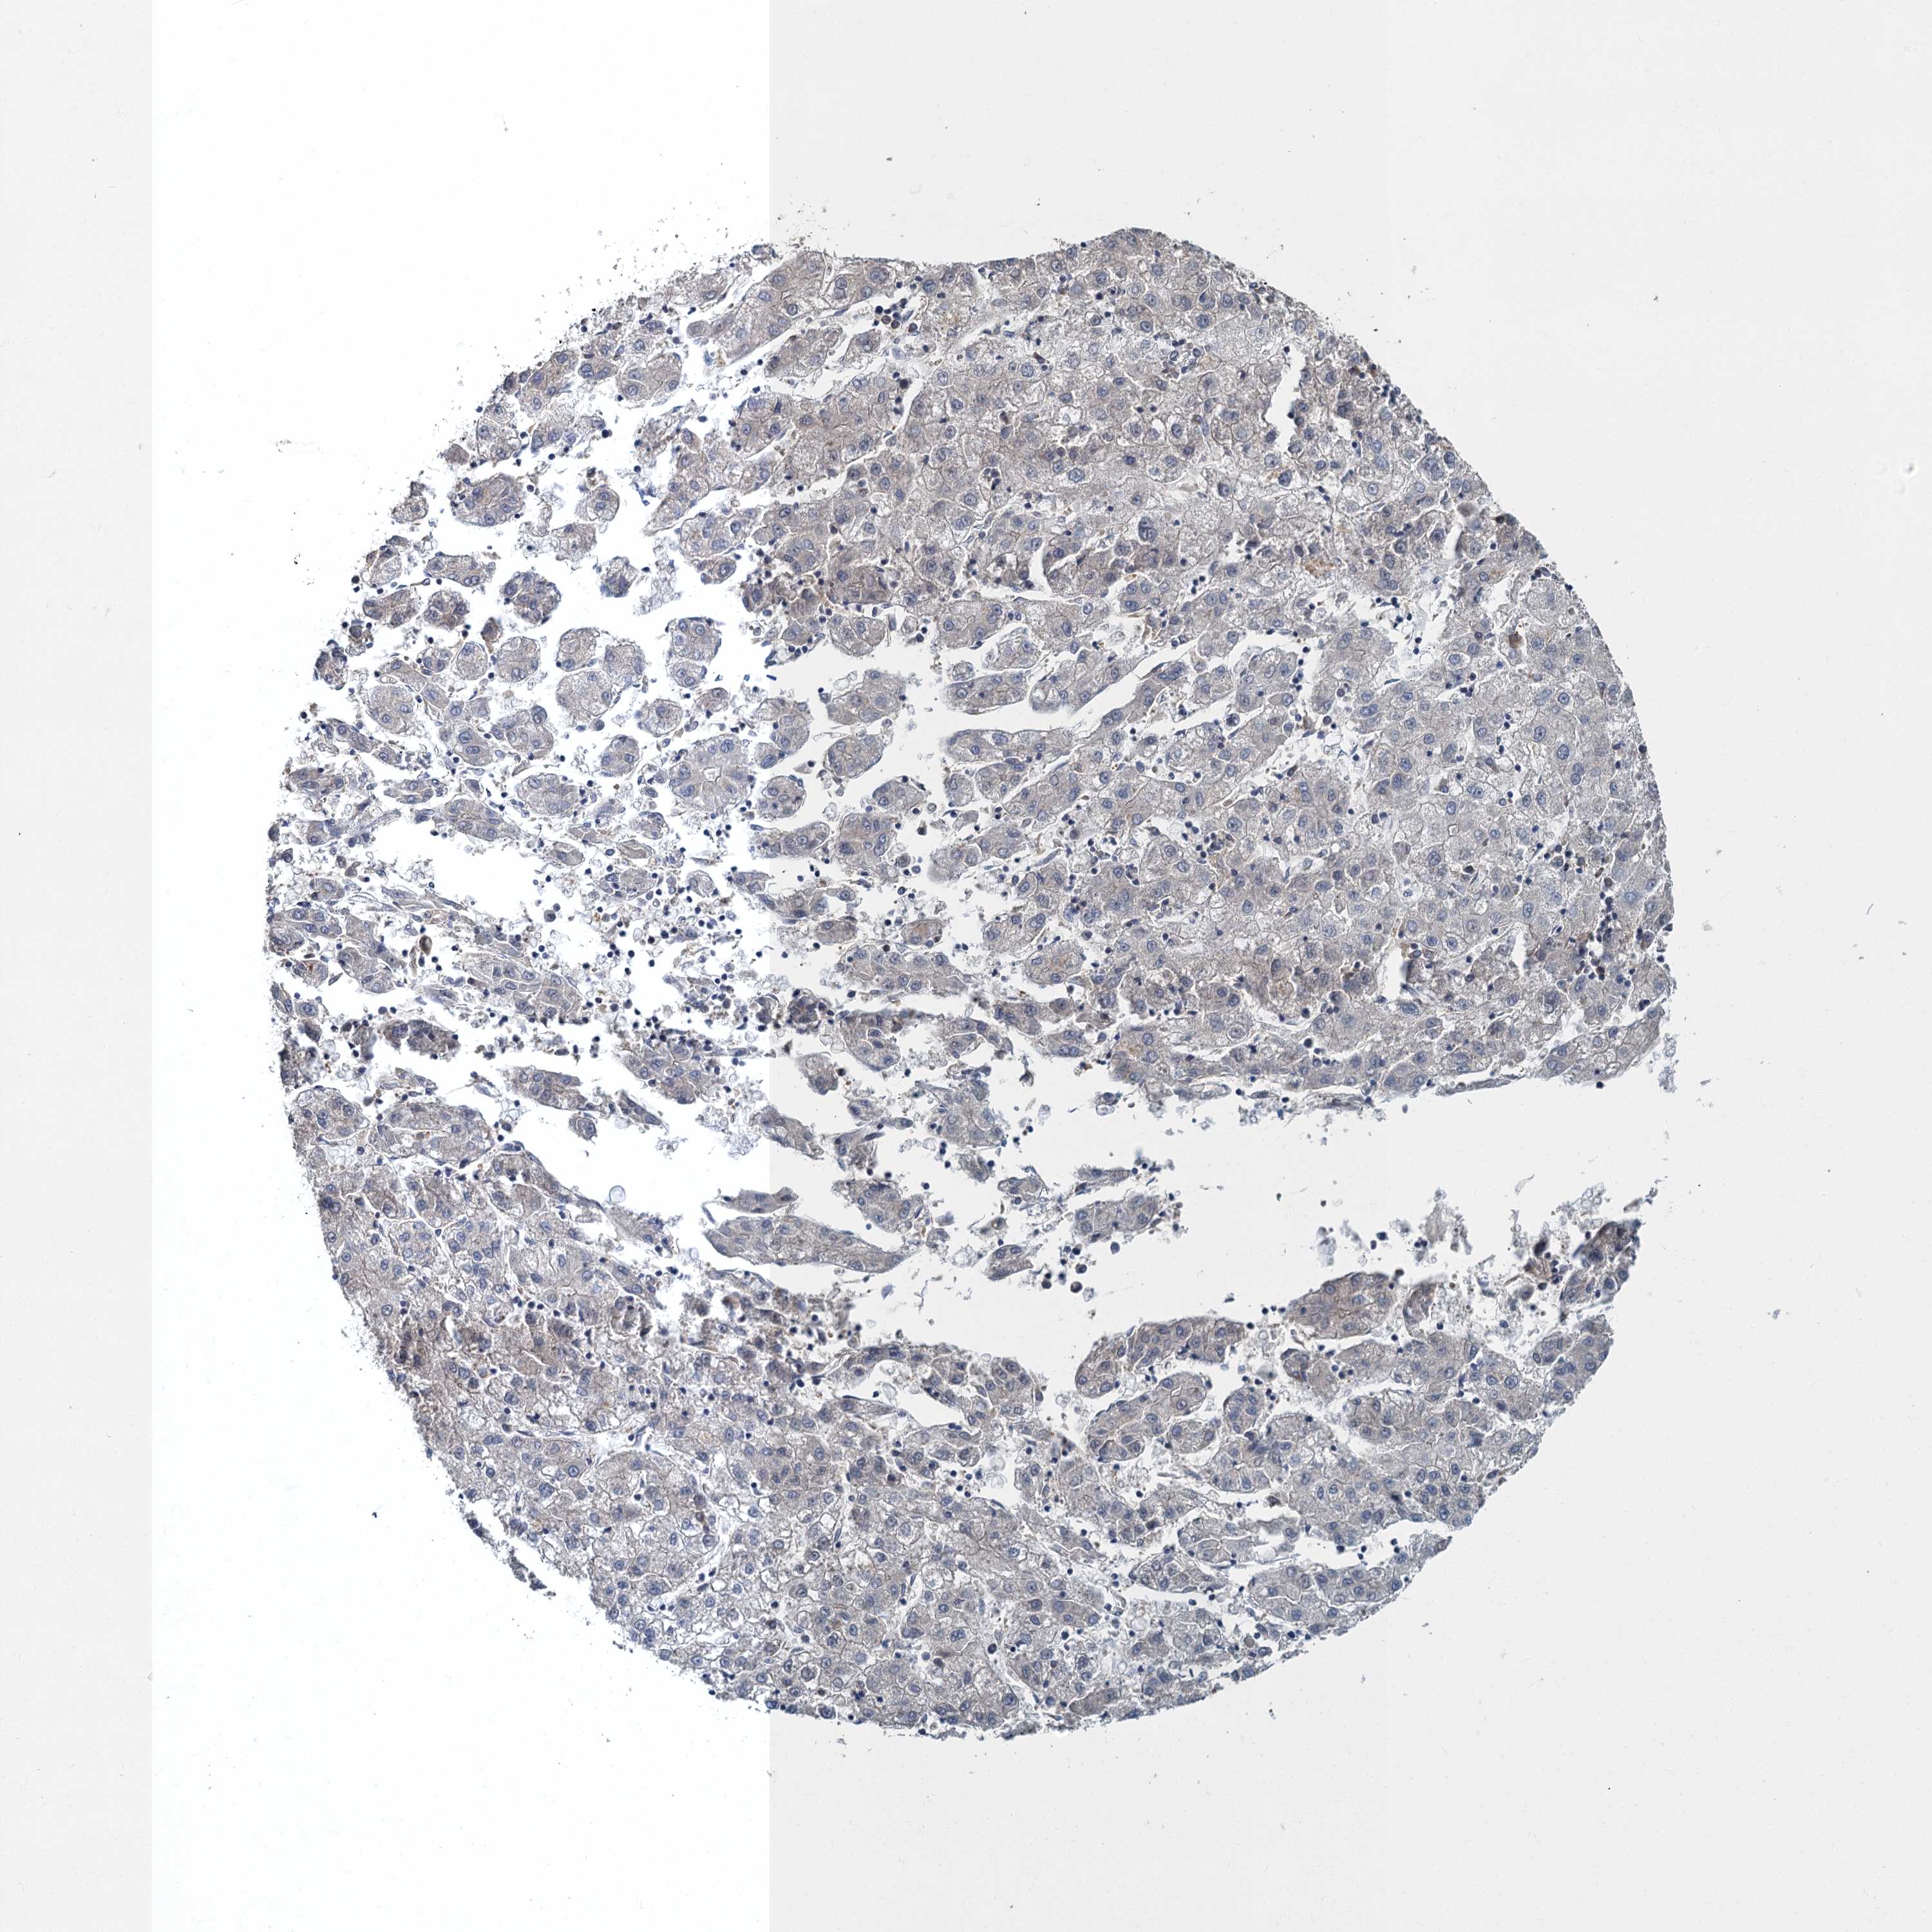

LIVER CANCER - Protein expressioni

A mouse-over function shows sample information and annotation data. Click on an image to view it in a full screen mode. Samples can be filtered based on level of antibody staining by selecting one or several of the following categories: high, medium, low and not detected. The assay and annotation is described here.

Note that samples used for immunohistochemistry by the Human Protein Atlas do not correspond to samples in the TCGA dataset.

Antibody stainingi

Antibody staining in the annotated cell types in the current human tissue is reported as not detected, low, medium, or high, based on conventional immunohistochemistry profiling in selected tissues. This score is based on the combination of the staining intensity and fraction of stained cells.

Each image is clickable and will lead to virtual microscopy that enables deeper exploration of all samples and also displays staining intensity scores, fraction scores and subcellular localization as well as patient and tissue information for each sample.

Antibody HPA039951

Staining

High

Medium

Low

Not detected

Intensity

Strong

Moderate

Weak

Negative

Quantity

>75%

75%-25%

<25%

None

Location

Nuclear

Cytoplasmic/membranous

Cytoplasmic/membranous,nuclear

Cholangiocarcinoma

Carcinoma, Hepatocellular, NOS